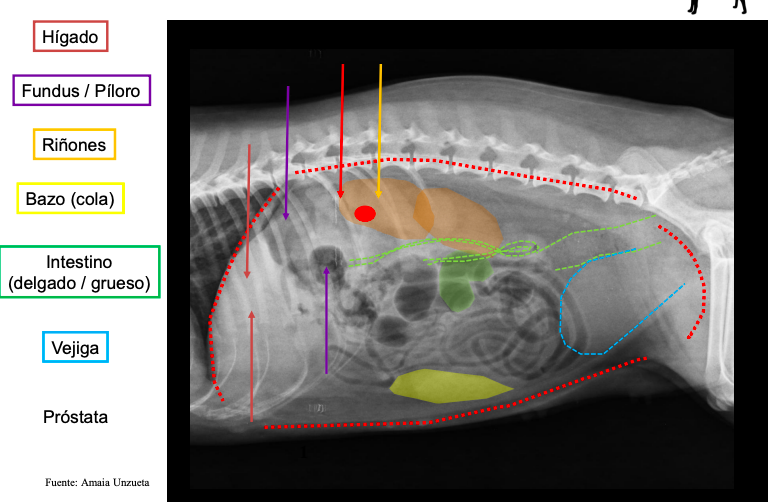

Bases anatómicas - Abdomen

esofago no se ve en radiografias. De craneal a caudal:

- Higado vesicula biliar a la derecha

- Estomago con pancreas

- Bazo (fundus a la izquierda, cola a la derecha en perros, gatos se mantiene medio-izquierdo)

- intestinos (asas intestinales) Colon ascendente derecho, descendente izquierdo

Radiografia laterolateral

Dependiendo de la posición los gases van a un lado o a otro: Decúbito lateral derecho Radiografía Lateral

- Gas en fundus

- Se ve mejor cola del bazo

- Mayor separación de siluetas renales

Decúbito lateral izquierdo

- Gas en píloro

- Mejor visualización delduodeno

Que NO se ve en una radiografia en condiciones normales

- Páncreas

- Glándulas adrenales

- Vesícula biliar

- Uréteres

- Uretra

- Nódulos linfáticos

- Vasos sanguíneos

- Ovarios

- Útero no gestante

Radiografia ventrodorsal